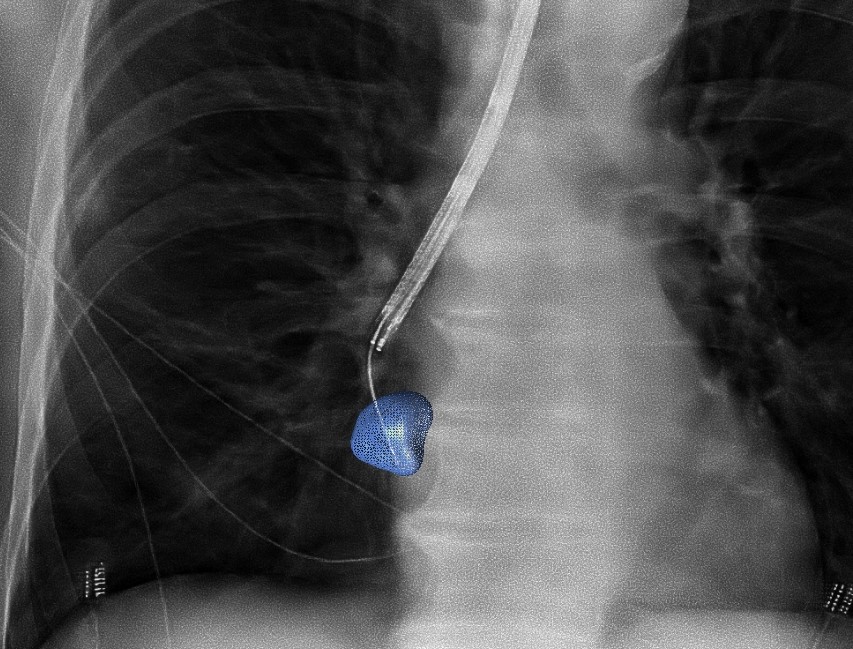

Radboudumc’s observational study reported the diagnostic accuracy and procedural radiation dose for patients undergoing an endobronchial lung biopsy supported by Philips Lung Suite - a solution that uses 3D imaging with augmented fluoroscopy to support high precision diagnosis and minimally-invasive therapy in one room. Diagnostic accuracy of 90% was reported while reducing the average total effective radiation dose per procedure by more than half from 47.5 Gy·cm2 (effective dose: 14.3 mSv) to 25.4 Gy·cm2 (effective dose: 5.8 mSv). The median long-axis diameter of the 248 lesions navigated to during the study was 13 mm (range 5-65mm). The results of the study were published in the October 2021 issue of the Journal of Bronchology & Interventional Pulmonology: Volume 28 - Issue 4 [1].

Philips Lung Suite enables all-in-one lung cancer diagnosis and treatment. It provides advanced real-time 3D imaging with augmented fluoroscopy on the company’s Image Guided Therapy System – Azurion, combined with dedicated software. With Philips’ Cone Beam CT imaging, the X-ray detector rotates around the patient to generate a CT-like image in around five seconds, providing clinicians with a high-resolution 3D view of the target lesion and other anatomical structures. This allows the clinician performing the biopsy procedure to be continually guided by high-quality real-time imaging to advance a catheter towards the lesion through a bronchoscope. Once done, its position can be confirmed in real-time using the same imaging modality and a biopsy sample removed.